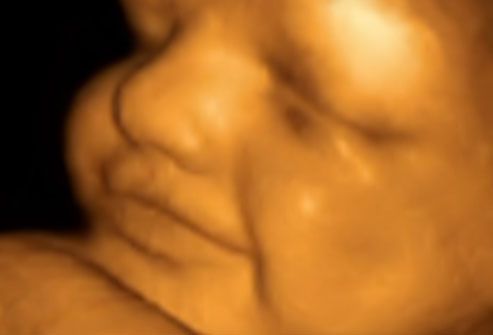

做超声波的时间

通常在怀孕20周时对孕妇进行超声波检查。在检查期间,医生要确保胎盘健康且附着正常,并且你的宝宝发育正常。你可以在超声波上看到婴儿的心跳以及身体、手臂和腿部的运动。通常可以在20周时确定婴儿的性别(当然,医生是不会告诉你的)。

20周时2D超声和4D超声的对比